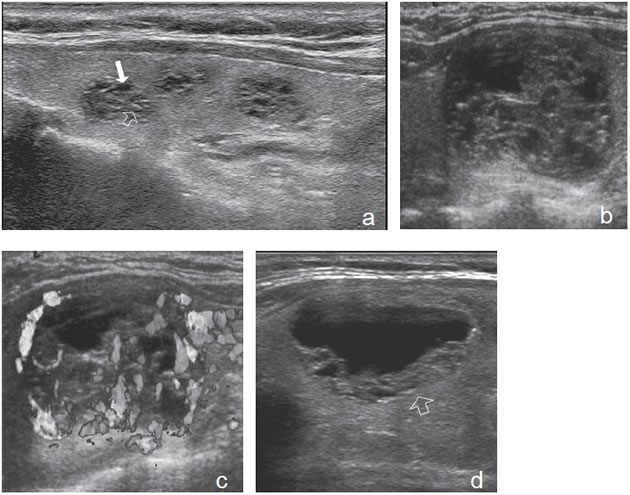

7. Invasión local y adenopatías

La extensión de la masa fuera de la cápsula, la infiltración de la tráquea o de los músculos pretiroideos es muy sugerente de malignidad (Figura 15a). Asímismo, la presencia de adenopatías con características típicas, debe hacer sospechar que el nódulo tiroideo es maligno. Los cánceres papilares de la tiroides son propensos a dar metástasis precozmente a los linfonodos cervicales y hasta la mitad de todos los pacientes pueden presentar adenopatías concomitantes. En 15% de los pacientes, el único signo de un cáncer tiroideo papilar oculto puede ser la detección de adenopatías. La mayoría de las metástasis ocurren ipsilateralmente al tumor primario en los grupos III y IV de la cadena yugular interna y del grupo VI del compartimiento central. En la ecografía, los linfonodos metastáticos pueden tener una forma redondeada o globular, una arquitectura con elementos sólidos o quísticos, con o sin microcalcificaciones y pérdida del hilio (Figura 15b y c). El “Doppler color” puede demostrar vasos capsulares de distribución caótica en reemplazo de los vasos hiliares normales (Figura 15d). Las adenopatías hiperecogénicas son sospechosas de cáncer papilar (Figura 16a). Los linfonodos normales en algunos grupos como el VI y el VII no se ven ecograficamente, de manera que si se hacen visibles, en el mismo lado del tumor, independiente del tamaño que tengan hay que considerarlos como adenopatías metastásicas (Figura 16b)

Figura 15. a) Cáncer papilar sólido de bordes lobulados (flechas) que muestra una gruesa calcificación central (flecha abierta) y múltiples

microcalcificaciones; b) Adenopatía cervical del grupo IV del mismo paciente (figura 15 a), hiperecogénica, con elementos quísticos (flecha

blanca) y microcalcificaciones agrupadas (flechas negras), típica de cáncer papilar; c) Adenopatías de grupo IV de un cáncer papilar, de

forma redondeada, hiperecogénicas, con pérdida del hilio, una anterior a la arteria carótida común (flecha) y otra lateral a la vena yugular

interna (flecha abierta); d) Corte sagital de la adenopatía lateral de la imagen 15 c), que en “doppler color” muestra vascularización patológica

y pérdida del hilio.

La apariencia ecográfica de los linfonodos metastásicos puede ser distinta a las del tumor primario y mostrar elementos quísticos y microcalcificaciones en mayor proporción que en el primario. En pacientes más jóvenes, las adenopatías puramente quísticas son relativamente comunes y cuando son solitarias pueden simular un quiste branquial o un quiste del conducto tirogloso.